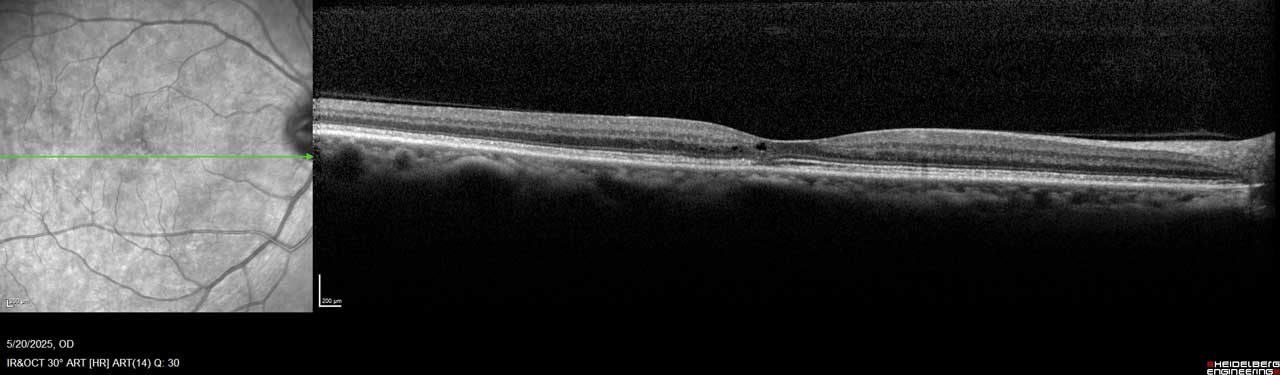

MacTel is believed to result from degeneration of Müller cells, the glial cells that surround and support neurons in the retina. This neurodegeneration leads to outer retinal atrophy and thinning, ultimately resulting in photoreceptor loss. In later stages, hyporeflective spaces in the outer retinal layer—most often within the foveal pit—can be observed on optical coherence tomography (OCT), indicating photoreceptor loss (Figure 1 and Figure 2).¹

Figure 1. This image of the right eye of a patient with MacTel type 2 shows a hyporeflective inner retinal cavity and loss of outer retinal signals, including photoreceptors temporal to the center of the macula.